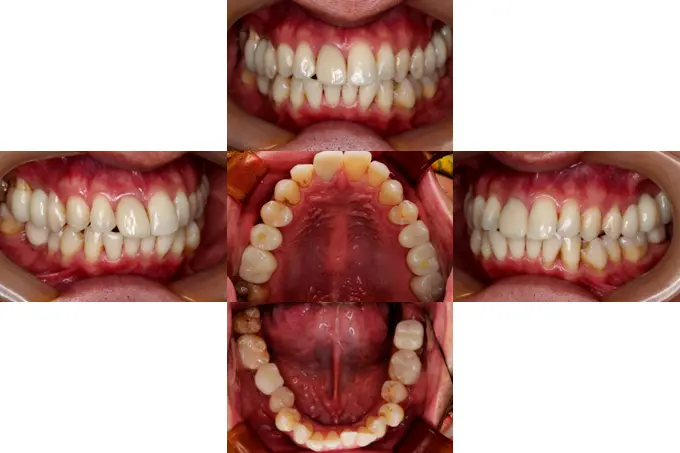

case14

症例14

| 治療ケース | 骨造成(GBR)、インプラント埋入、オールセラミッククラウン、all on 4 |

| 症状 | 咬みにくい |

| 治療結果 | 歯のない所を治療したいとの主訴で来院されました。虫歯や破折で抜歯が必要な状態でした。抜歯、骨造成(GBR)を行い待機期間を経て1次手術、2次手術を行いプロビジョナルを装着後問題の無いことを確認して最終上部構造を装着。歯が入った後経過も良く、安定している状態です。 |

| 治療開始月 | 2024年7月 |

| 治療期間 | 約10ヶ月 |